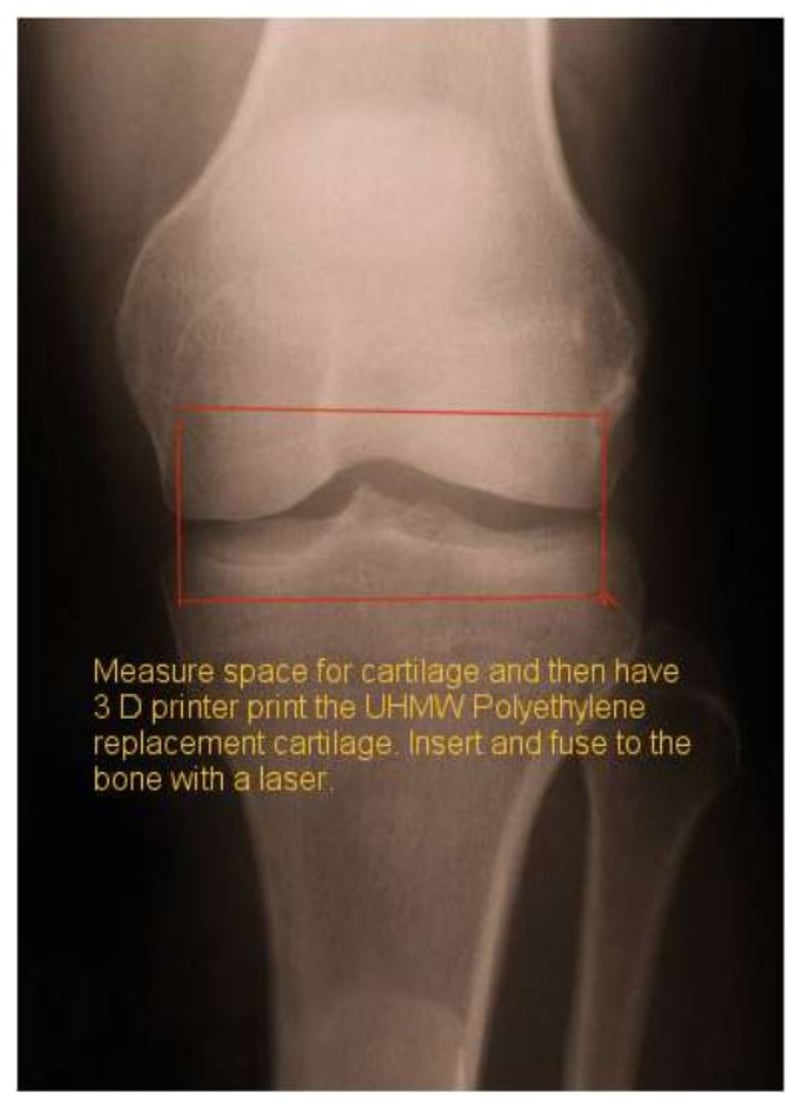

Using current imaging technology, get measurements of the cartilage space in the joint. Then with a 3 D printer, print the replacement cartilage our of ultrahigh molecular polyethylene (or similar wear resistant polymer). After printing the replacement cartilage, insert it in the joint and fuse to the bone with laser.

This should be able to be done with a small incision and not injuring the ligaments/tendons around the joint.

As 3D printers evolve to allowing printing of various alloys of metals, metal replacement cartilage could become the standard for wear resistance and durability.

This would save major surgery for replacement implants as used today.